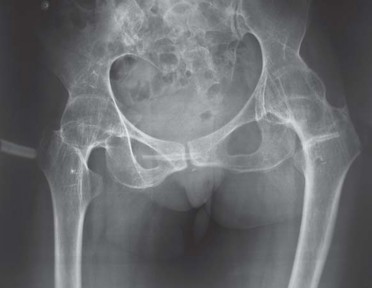

يميل مرضى التهاب المفاصل الروماتويدي اليفعي إلى امتلاك قناة نخاعية فخذية ضيقة جدًا مع عدم توافق بين قطر القناة القريبة والبعيدة. يمكن أن يختلف التجويف الحقي من النوع المشوه (كما يظهر في الشكل 29.1) إلى النوع المنغمس (كما يظهر في الشكل 29.2) أو قد يكون مفصل ورك ملتحم (كما يظهر في الشكل 29.3).

انصهار ثنائي في مفصل الورك بالتهاب المفاصل اليفعي